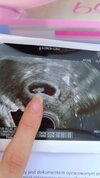

Jest ponad centymetr człowieczka z bijącym sercem ❤️🥰 🥹🥹 7+3, termin na 12.02 czyli wszystko dokładnie tak, jak sobie wyliczyłam sama na początku z owulacji ;) z ostatnia miesiączka mam tygodniowy rozjazd, ale mam cykle 33 i więcej i wiedziałam że standardowe liczenie nie ma sensu w moim przypadku ;)

Sorki za paluch na zdjęciu ale robiłam na szybko dla męża :P wiecie, trzeba było dokładnie pokazać 😅

Mąż przeszczęśliwy, siedział jak na szpilkach te dwa tygodnie, bo bał się czy maluch sie pojawi.